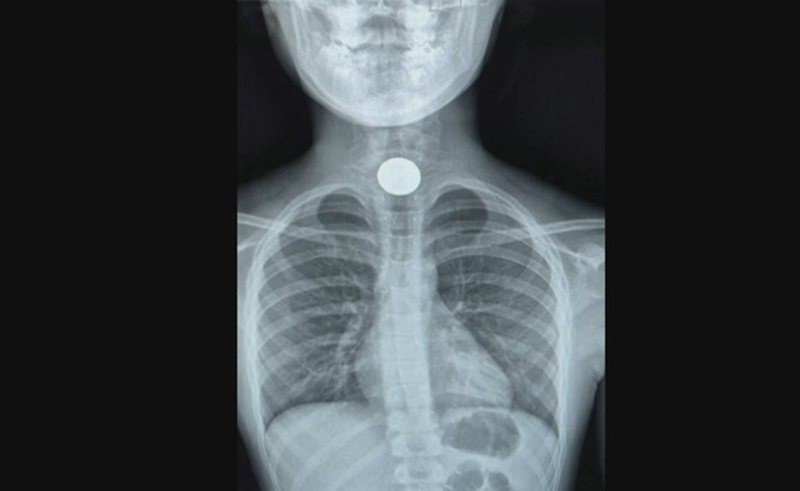

בבית החולים הציבורי אסותא באשדוד שמו לב לתופעה מוזרה - שתי ילדות הגיעו למיון אחרי שבלעו מטבעות. בצילומי הרנטגן ניתן לראות את המטבע - כשהוא תקוע בדרכי הנשימה. אחת הילדות אף נאלצה לעבור ניתוח כדי להוציא את המטבע, כך פורסם לראשונה במהדורה המרכזית של חדשות 12.